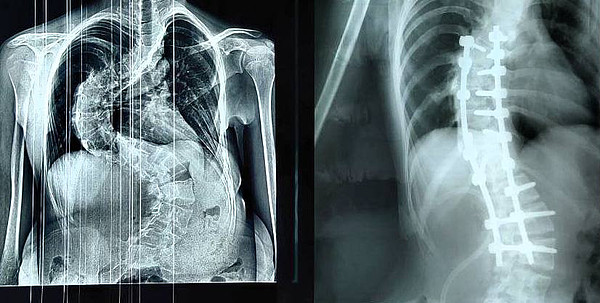

Кировские травматологи-ортопеды лечат тяжелые формы сколиоза